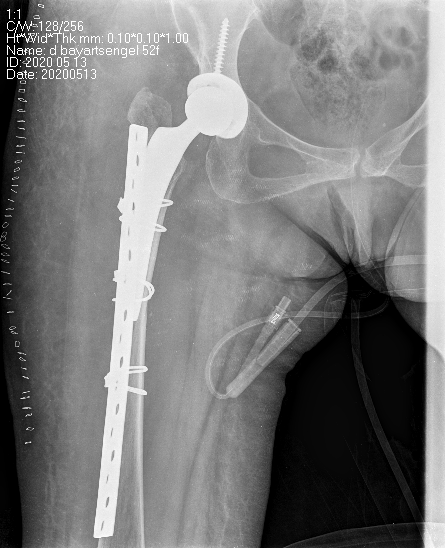

Дунд чөмөгний хүзүүний эмгэг хугарлын мэс заслын эмчилгээний сонголт:

Internal Fixation-хагалгаа, дотор бэхэлгээ / тусгай хадаас

DHS - Дунд чөмөгний гадна бэхэлгээ

УНТЭ-т хийгдсэн мэс заслын зураг

Hip screw-Түнхний шураг